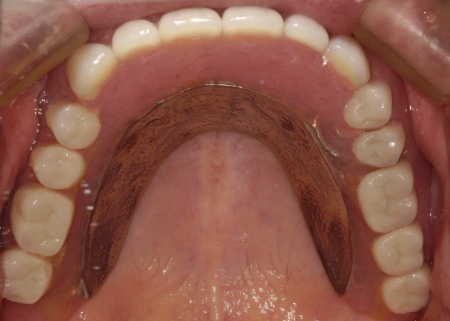

次に上下顎に装着するため、チタン床を使用した金属床義歯を作製しました。

チタンは軽量でありながら強度が高く、体になじみやすい特徴をもつ素材です。また、金属床にすることで従来の樹脂製義歯と比べて薄く作ることが可能になり、装着による違和感の軽減も見込めます。

また、上顎は残存歯が少ないためすべてを覆う総入れ歯で、下顎は前歯がしっかり残っているため部分入れ歯の形で作製しました。

完成した入れ歯を装着していただき、噛み合わせや義歯の安定性、見た目の仕上がりに問題がないことを確認して、治療を終了しています。